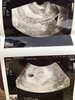

Przestałam dostawać powiadomienia i myślałam, ze nikt tu już nie pisze. Wczoraj byłam na usg. Wg usg 5t5d, lekarz twierdzi ze po prostu później zaczęła się rozwijać (bo kiedy byla owulacja to wiemy, miałam robiony zastrzyk). Trochę mnie to zasmuciło, ale lekarz mówi, ze wszystko ok. Zarodek ma 2 mm. Akcji serduszka jeszcze nie ma, idę za tydzień w czwartek.